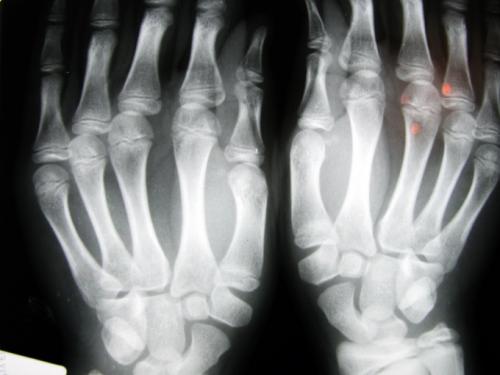

Определить, что ваш палец выбит, можно по следующим признакам: припухлость, появление подкожной гематомы , боль при сгибании. Следует отметить, что окончательный диагноз можно установить только при рентгенологическом исследовании.

Помните, что под симптомами выбитого пальца могут маскироваться и разрывы сухожилий, и трещины кости, и переломы. Для того чтобы исключить эти диагнозы, необходимо как можно скорее обратиться к врачу-травматологу, который осмотрит повреждение и назначит рентген. Если повреждения руки окажутся серьезными, то вам может быть показана операция или гипсовая иммобилизация. Именно поэтому при любой травме не стоит заниматься самолечением, а лучше сразу же обратиться к специалисту.